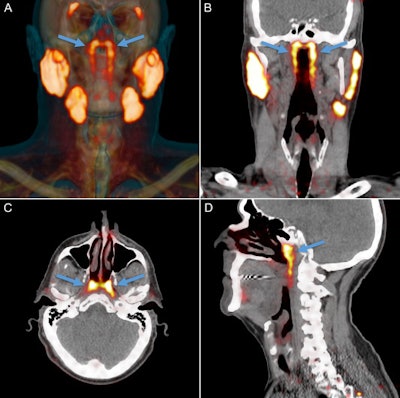

Positron emission tomography (PET)/computed tomography (CT) with radiolabeled ligands to prostate-specific membrane antigen (PSMA), a well-characterized imaging biomarker for prostate cancer, visualized the glands, which are being referred to as tubarial glands. Sparing these glands may help prevent radiotherapy (RT) side effects, such as dry mouth, and help head and neck cancer (HNC) patients maintain better quality of life, according to authors.

The newer molecular imaging modality PSMA-PET/CT can visualize salivary glands with high sensitivity and specificity, Valstar and colleagues wrote. This allowed the researchers to observe an unknown bilateral structure posterior in the nasopharynx, with ligand uptake much like that of the known major parotid, submandibular, and sublingual salivary glands.

All 100 patients with prostate or urethral gland cancer demonstrated a divided bilateral PSMA-positive area with an average length of 4 cm. Examining the glands and 3D reconstruction confirmed the presence of PSMA-expressing, predominantly mucous glands with multiple draining ducts. They were found predominantly near the torus tubarius, according to the authors.